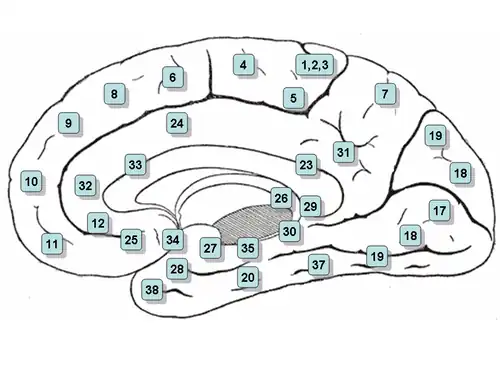

- Vía óptica: a través del núcleo geniculado lateral hacia el área 17 de Brodman.

- Vía auditiva: a través del núcleo geniculado medial hacia las áreas 41-42 de Brodman.

- Señales sensoriales del hemicuerpo y hemicara contralateral: a través del núcleo ventral posterolateral hacia las áreas 1-2-3 de Brodman.

- Cerebelo y globo pálido: a través del núcleo ventral anterior y núcleo vental lateral hacia el área 6 de Brodmann.

- Cuerpos mamilares: a través de núcleo anterior del tálamo hacia la circunvolución del cíngulo.

- Corteza prefrontal: a través del núcleo dorsomedial.[5]